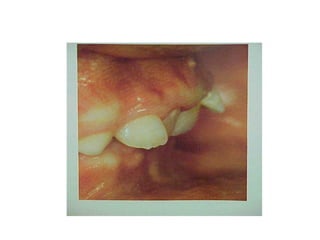

CLASE III DE ANGLE.

CLASE III DE ANGLE

En la clase III de Angle: El molar inferior se encuentra situado

mesialmente respecto de la relación molar normal. La línea de

oclusión puede aparecer correcta o incorrecta.

MALOCLUSIONES DE LA CLASE III

Mordida cruzada anterior y posterior.

Mandíbulas grandes y maxilares superiores pequeños.

La relación incisiva puede y suele estar invertida, con los

incisivos superiores ocluyendo por palatino de los inferiores.